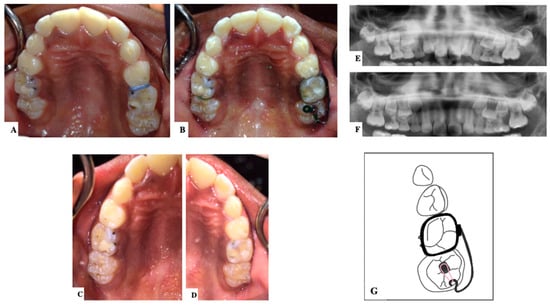

11. Novel Devices